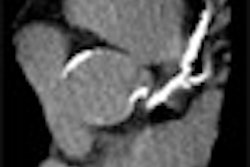

The patients, who were imaged in a weight-bearing position, had pelvic x-rays performed with 15 ± 5° internal rotation of the feet and at 0.7 mSv. For hip AP views, the same foot rotation was used but the x-ray beam was fluoroscopically directed at the joint space. The radiation exposure for the latter was 0.3 mSv. Finally, oblique views were obtained at an exposure rate of 0.3 mSv. The JSW of the hip joint was measured at the narrowest point for each view.